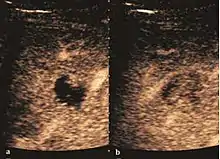

Hemangioma

It is the most common liver tumor with a prevalence of 0.4 – 7.4%. It is generally asymptomatic but also can be associated with pain complaints or cytopenia and/or anemia when it is very bulky. It is unique or paucilocular. It can be associated with other types of benign liver tumors. Characteristic 2D ultrasound appearance is that of a very well defined lesion, with sizes of 2–3 cm or less, showing increased echogenity and, when located in contact with the diaphragm, a "mirror image" phenomenon can be seen. When palpating the liver with the transducer the hemangioma is compressible sending reverberations backwards. Doppler exploration reveals no circulatory signal due to very slow flow speed. CEUS investigation has real diagnosis value due to the typical behavior of progressive CA enhancement of the tumor from the periphery towards the center. The enhancement is slow, during several minutes, depending on the size of hemangioma and on the presence (or absence) of internal thrombosis. During late (sinusoidal) phase, if totally "filled" with CA, hemangioma appears isoechoic to the liver. Deviations from the above described behavior can occur in arterialized hemangiomas or those containing arterio-venous shunts. In these cases, differentiation from a malignant tumor is difficult and requires other imaging procedures, follow up and measurements of the tumor at short time intervals.[4]